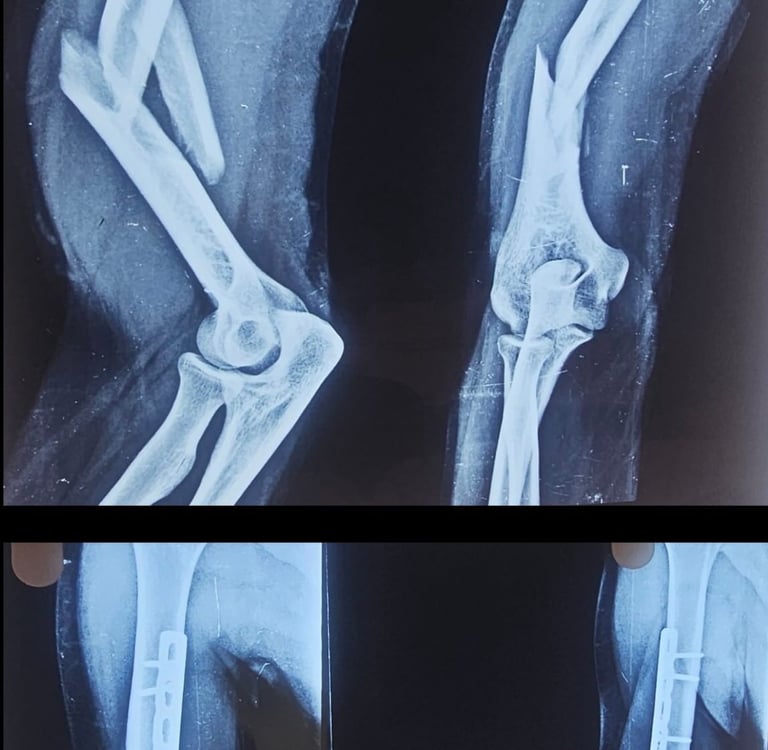

Fractures

Expert surgical care for complex and open bone fractures to restore strength.

Revisions

Correcting previous surgeries and healing stubborn non-union fractures with precision.